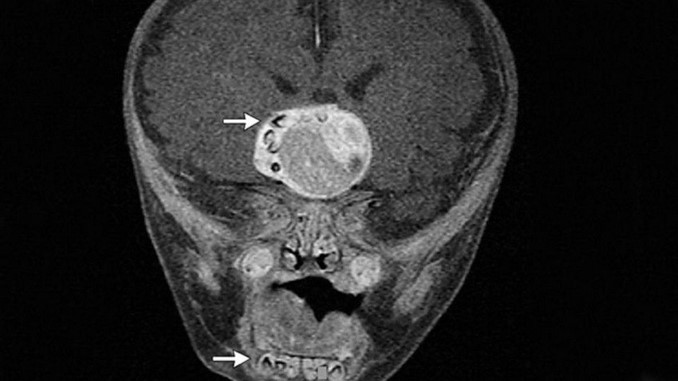

Un sorprendente caso fue publicado en el “New England Journal of Medicine” en el cual explica lo sucedido a un bebé de 4 meses quien presentó un crecimiento anormal en la glándula pituitaria en la base del cerebro, lo peculiar fue que al extraer el tumor también se encontraron con varios dientes.

Los médicos al notar una masa extraña en la cabeza del bebé procedieron a realizarle varias pruebas que comprobaron que en efecto se trataba de un crecimiento desmedido de la glándula pituitaria, denominado tumor por su comportamiento, pero por fortuna benigno.

Programaron una cirugía para a realizar la extracción de este, sin embargo en el procedimiento se encontraron con varios dientes en crecimiento alrededor de la masa de células de la glándula.

Los médicos lograron determinar que se trataba de un extraño tumor denominado craneofaringioma, los cuales históricamente se parecen mucho a algunos tumores o quistes odontogénicos.